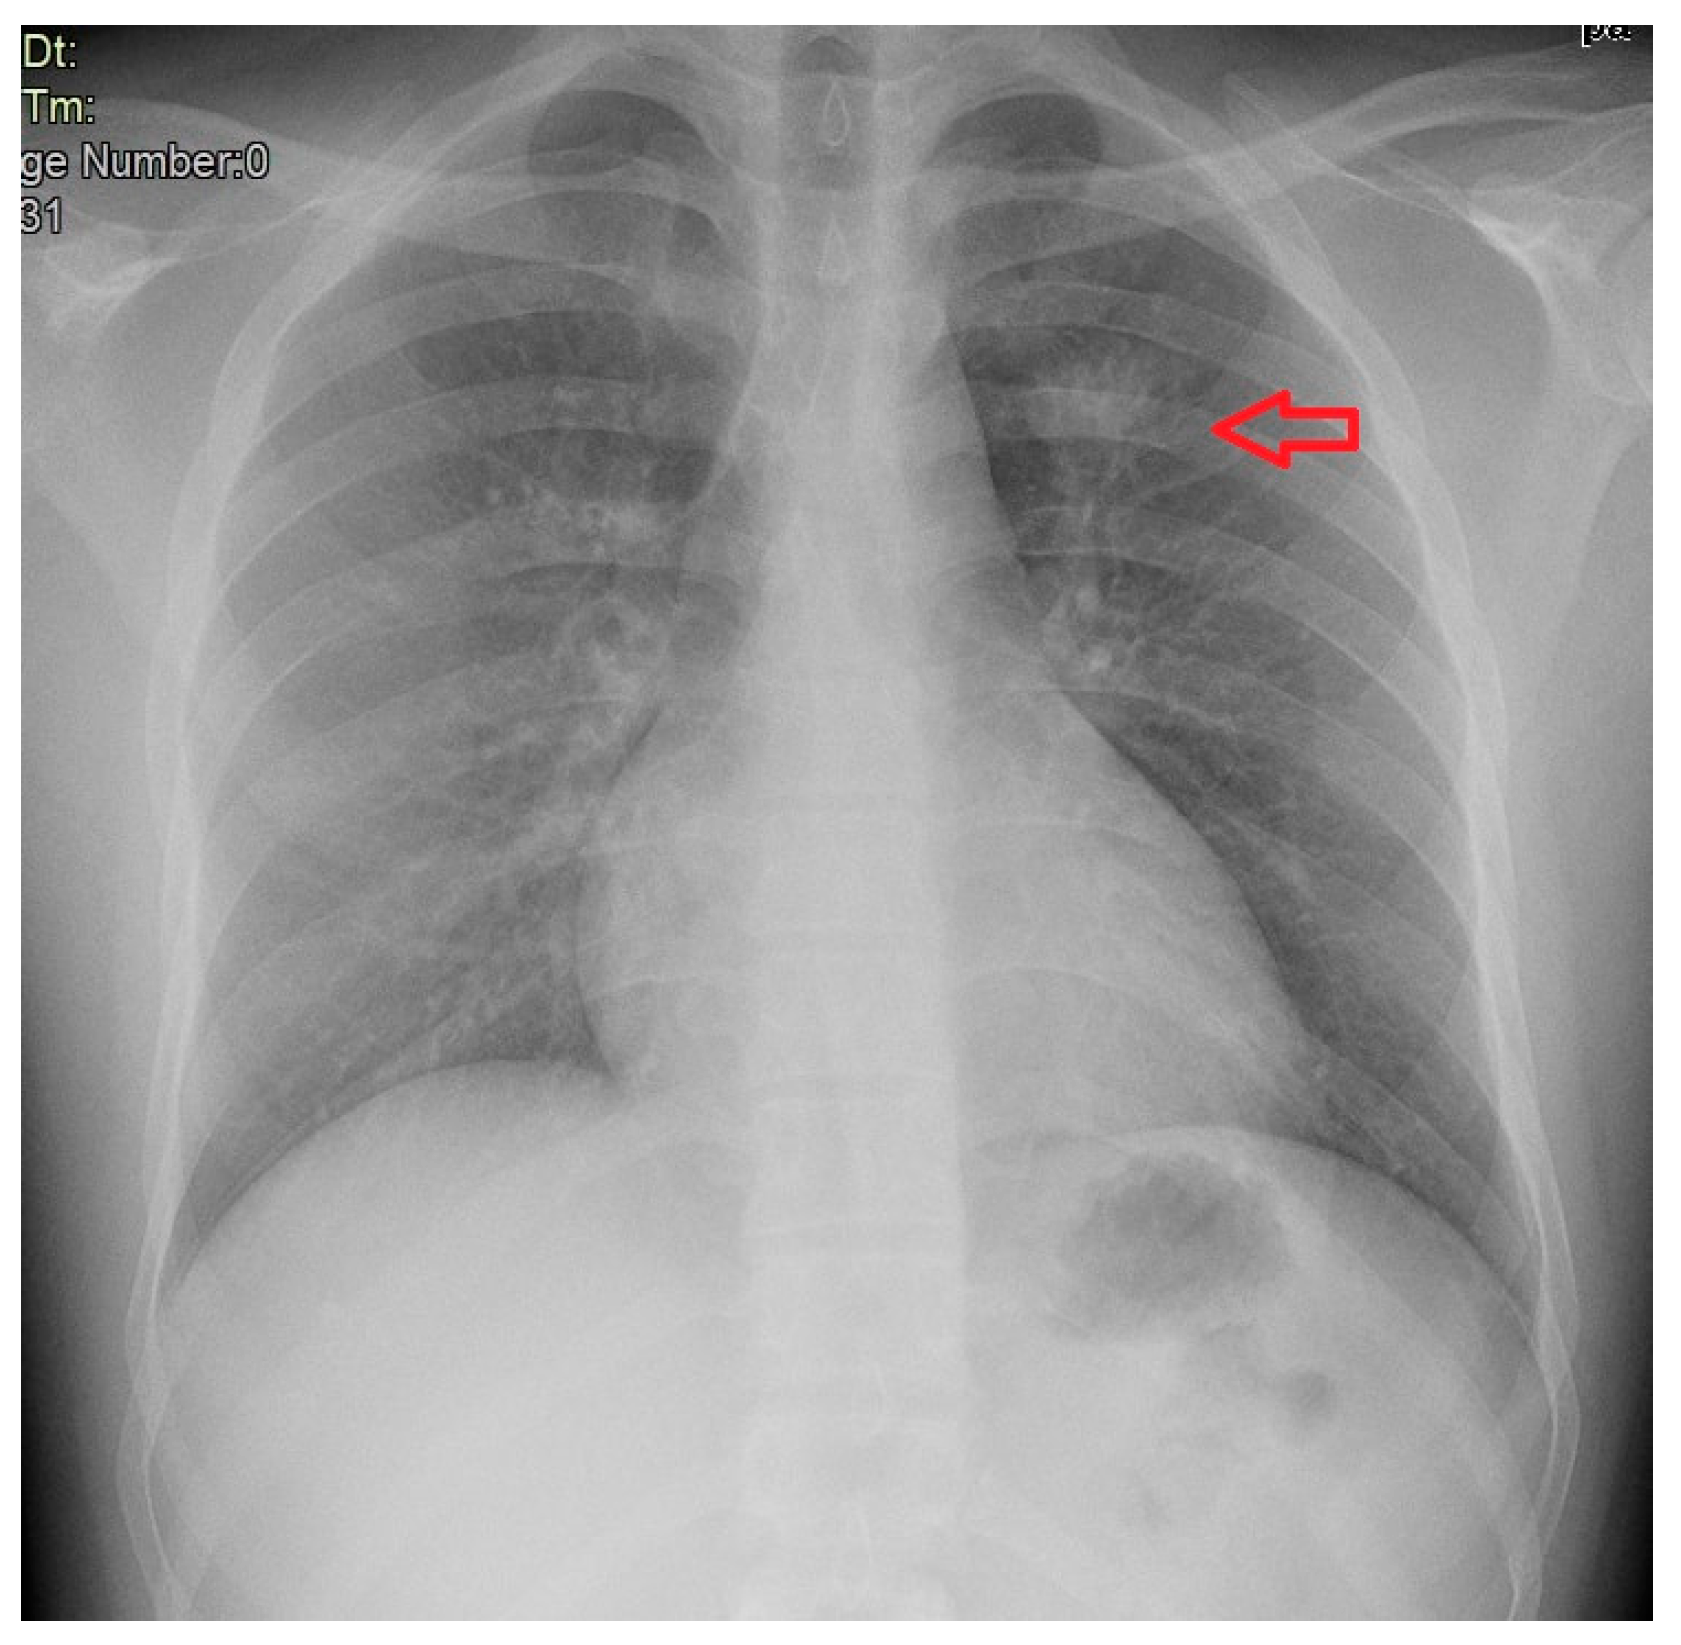

3. Case Description

4. Clinical Case Management